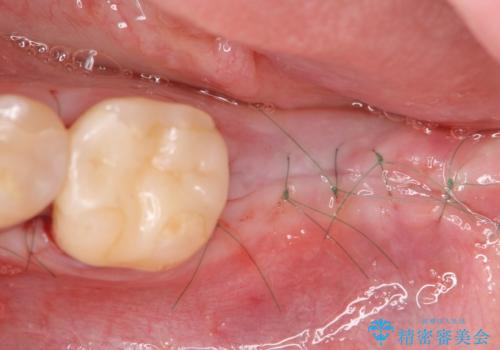

- 8ヶ月

- 5-10回